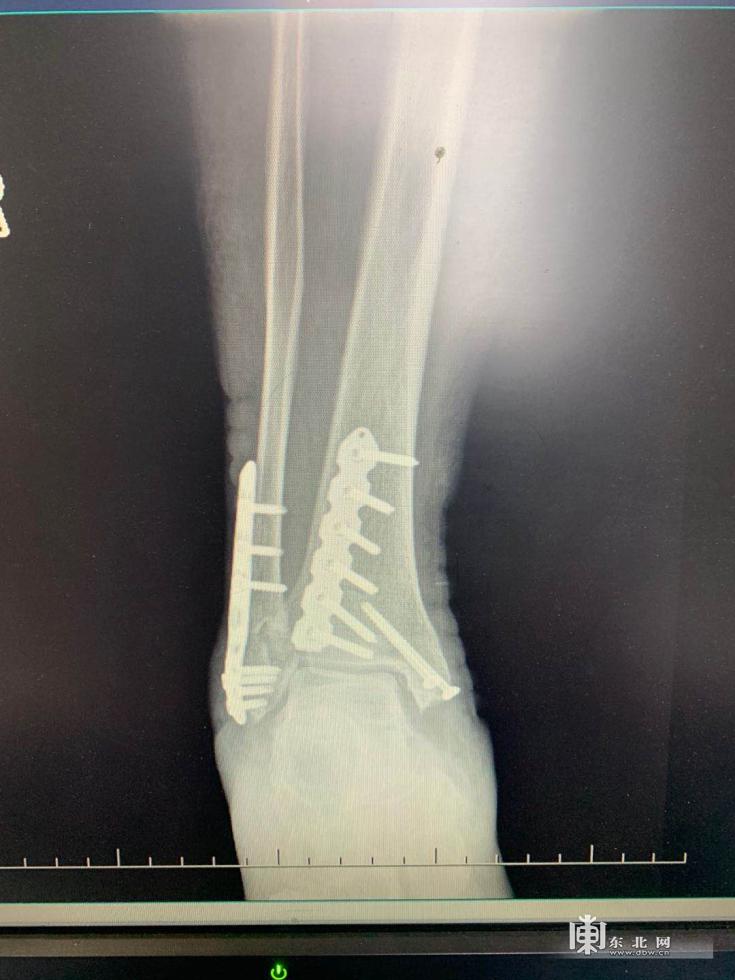

患者术后X射线图像

影像学检查结果显示,周女士为右侧足踝三踝粉碎性骨折,属于足踝骨折里的重度骨折,这个结果让周女士和家人都感觉到奇怪。只是崴到了脚踝,怎么一下子就骨折了呢?还是三踝骨折!

据哈尔滨市第五医院骨科五病区医生苏郁介绍,在日常门诊接诊时也会有多踝骨折的患者,但是像周女士这种三踝骨折的情况相对较少,而且是粉碎性骨折。根据苏郁了解周女士的既往病史和生活习惯并配合骨密度检查,周女士属于骨质疏松,正是因为骨质疏松才导致这次受伤如此严重。因为伤情严重,周女士想赶紧手术。但是苏郁医生表示手术还需要完善相关检查以及等待一个最佳的“时机”。苏郁表示,这里指的“时机”是指手术的最佳时间。因为踝关节周围的软策划比较薄,一旦受伤后软策划挫伤的情况比较重。所以在手术之前,要经过严格的消肿。如果肿胀不消除,术后感染的风险也比较高,特别是像这种复杂的多踝骨折。所以踝关节骨折手术时机的选择也比较重要。苏郁医生与骨科五病区白云星主任反复商讨手术方案,决定为其进行“右侧三踝粉碎性骨折切开复位内固定”。术中,医生们选择了从右踝内侧和后外侧进行切口,同时利用后外侧切口联合固定外踝和后踝,最大限度减少患者软策划损伤的程度,减少皮肤坏死的几率。术后周女士恢复良好,现已自行出院回家修养。